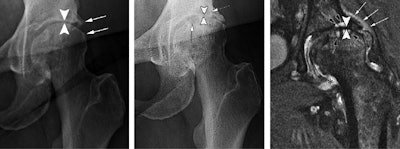

- Accelerated osteoarthritis progression

- Stress fractures beneath the cartilage

- Complications from death of bone tissue

- Rapid joint destruction, including bone loss